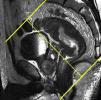

Estudio del tercio inferior del rectoHan de obtenerse planos coronales estrictos y oblicuos sobre la adquisición sagital que relacionen el tumor con el suelo pélvico y esfínteres o el tumor con el canal anal (figs. 10 y 11). Las imágenes resultantes son fundamentales para la cirugía con preservación de esfínteres14. Ha de destacarse que la diferenciación entre las capas propias del recto suele ser imposible en el tercio inferior1.